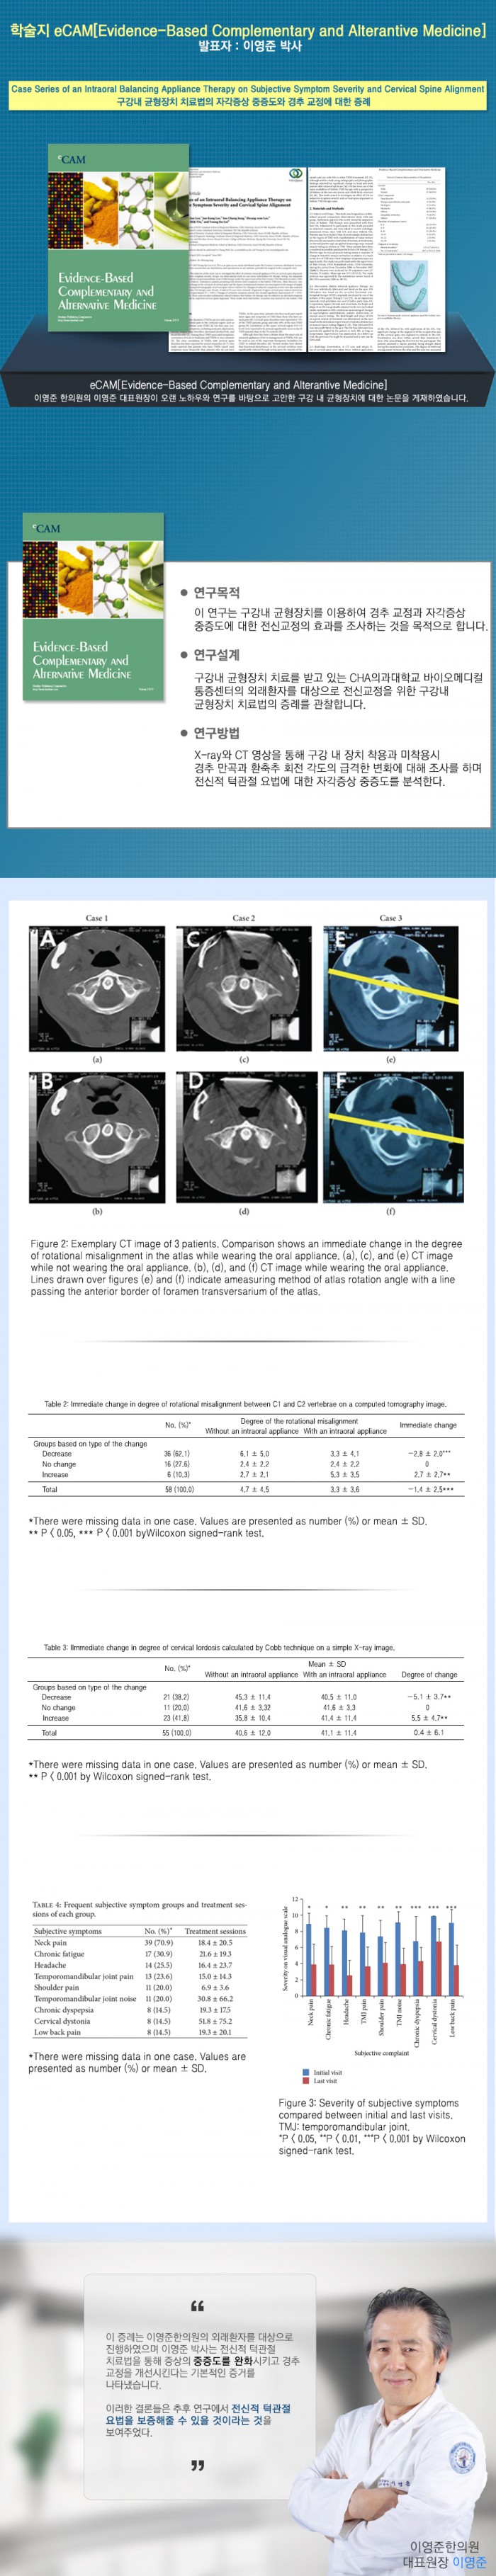

Case Series of an Intraoral Balancing Appliance Therapy on Subjective Symptom Severity and Cervical …